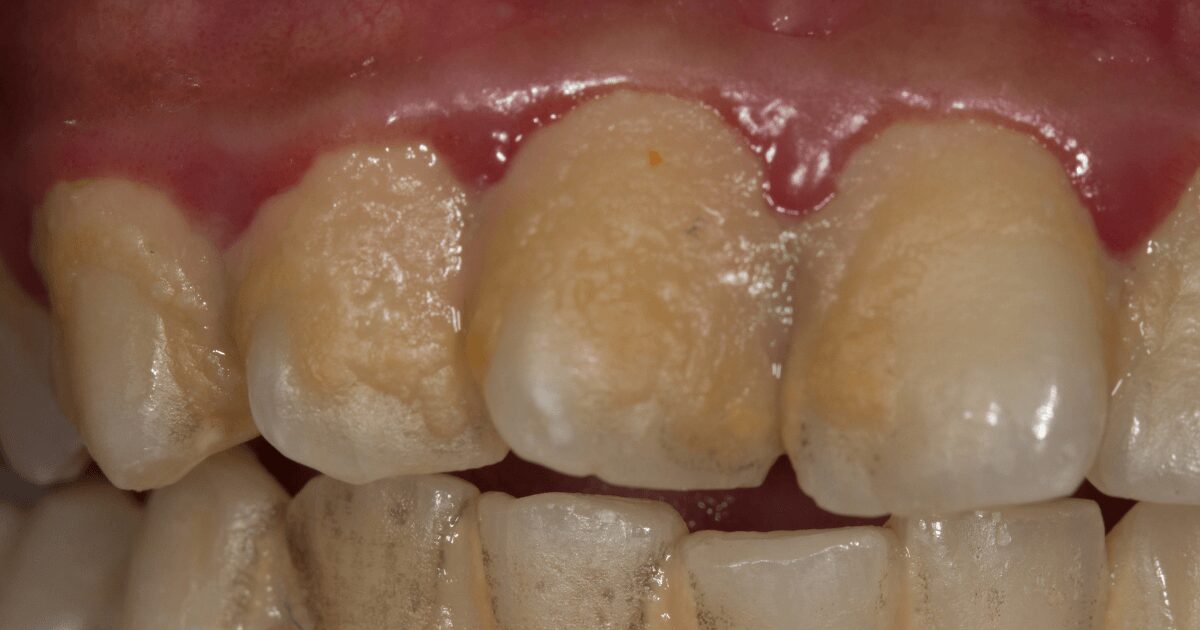

① 歯肉炎

歯周病のもっとも初期の状態です。

歯ぐきに炎症が起こり、歯を磨いたときに出血したり、赤く腫れたりすることがあります。

この段階では、まだ歯を支える骨には影響がありません。

② 軽度歯周病

歯ぐきの炎症が進み、歯を支える骨が少しずつ溶け始めます。

歯と歯ぐきの間にすき間(歯周ポケット)ができ、汚れがたまりやすくなります。

この頃から、冷たいものがしみる・歯ぐきが腫れる・口臭が気になるなどの症状が出ることもあります。